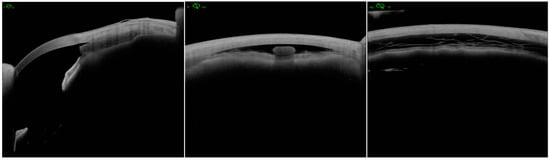

Figure 2. (a,b) Ultrasound biomicroscopy of MINIject showing a supraciliary cleft and a reservoir of aqueous humor drainage; (c) Anterior segment optical coherence tomography of MINIject showing a reservoir of aqueous humor drainage.